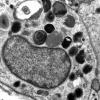

PERIPHERAL NEUROPATHY

17 TOXIC NEUROPATHIES

Amiodarone (2)